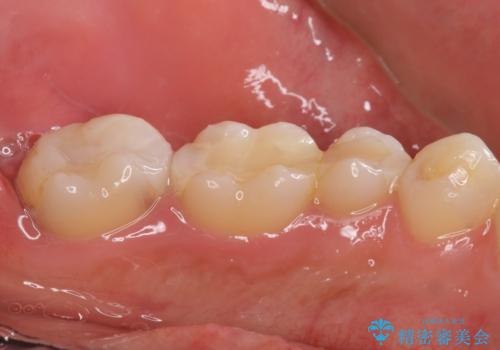

精査したところ、ほとんどの歯が保険内のレジンで充填されており、咬み合わせも悪く咬合していない歯もありました。

虫歯をしっかりと治療したのち、オールセラミッククラウンによる補綴治療を行いました。

憧れのヴィジュアル系バンドマンのような白い歯になり、喜んで下さいました。

不適なレジン充填によるデコボコがなくなったことで歯磨きしやすくなり、また気にされていた咬み合わせも良くなり、ご満足頂けました。

クラウンの種類:オールセラミッククラウン スタンダード

シェード:NW0